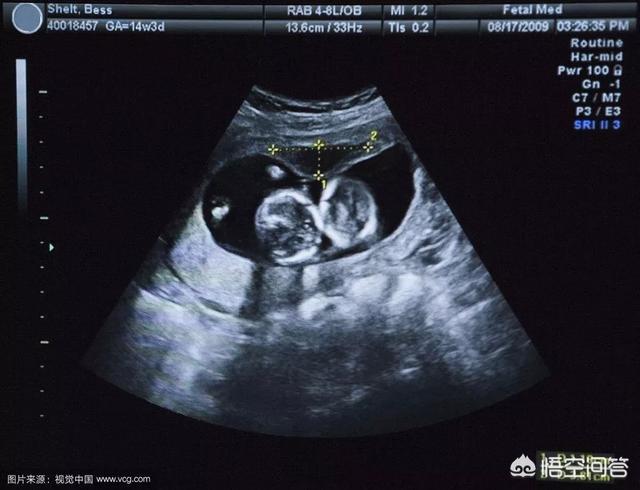

②, l'échographie pour vérifier l'emplacement du sac gestationnel, mais le sac gestationnel dans le premier mois de la grossesse est trop petit peut ne pas être en mesure de voir, il est donc recommandé que les mères enceintes peuvent attendre jusqu'au 42e jour de la grossesse pour vérifier.

Une fois de plus, une échographie gynécologique doit être effectuée pour clarifier l'emplacement du sac gestationnel et exclure une grossesse extra-utérine ou d'autres anomalies. Si le sac gestationnel n'est pas visible pour l'instant, vous pouvez en examiner un ultérieurement !